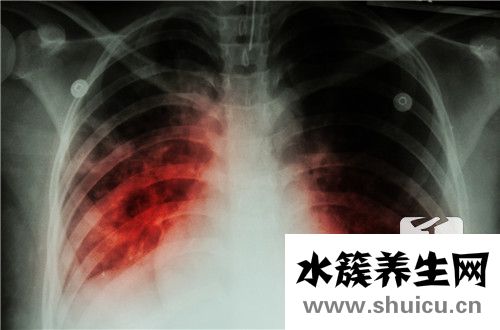

相關檢查有:心電圖,X線檢查,超聲心動圖,放射性核素與磁共振成像(MRI)檢查,運動耐量和運動峰耗氧量測定等。